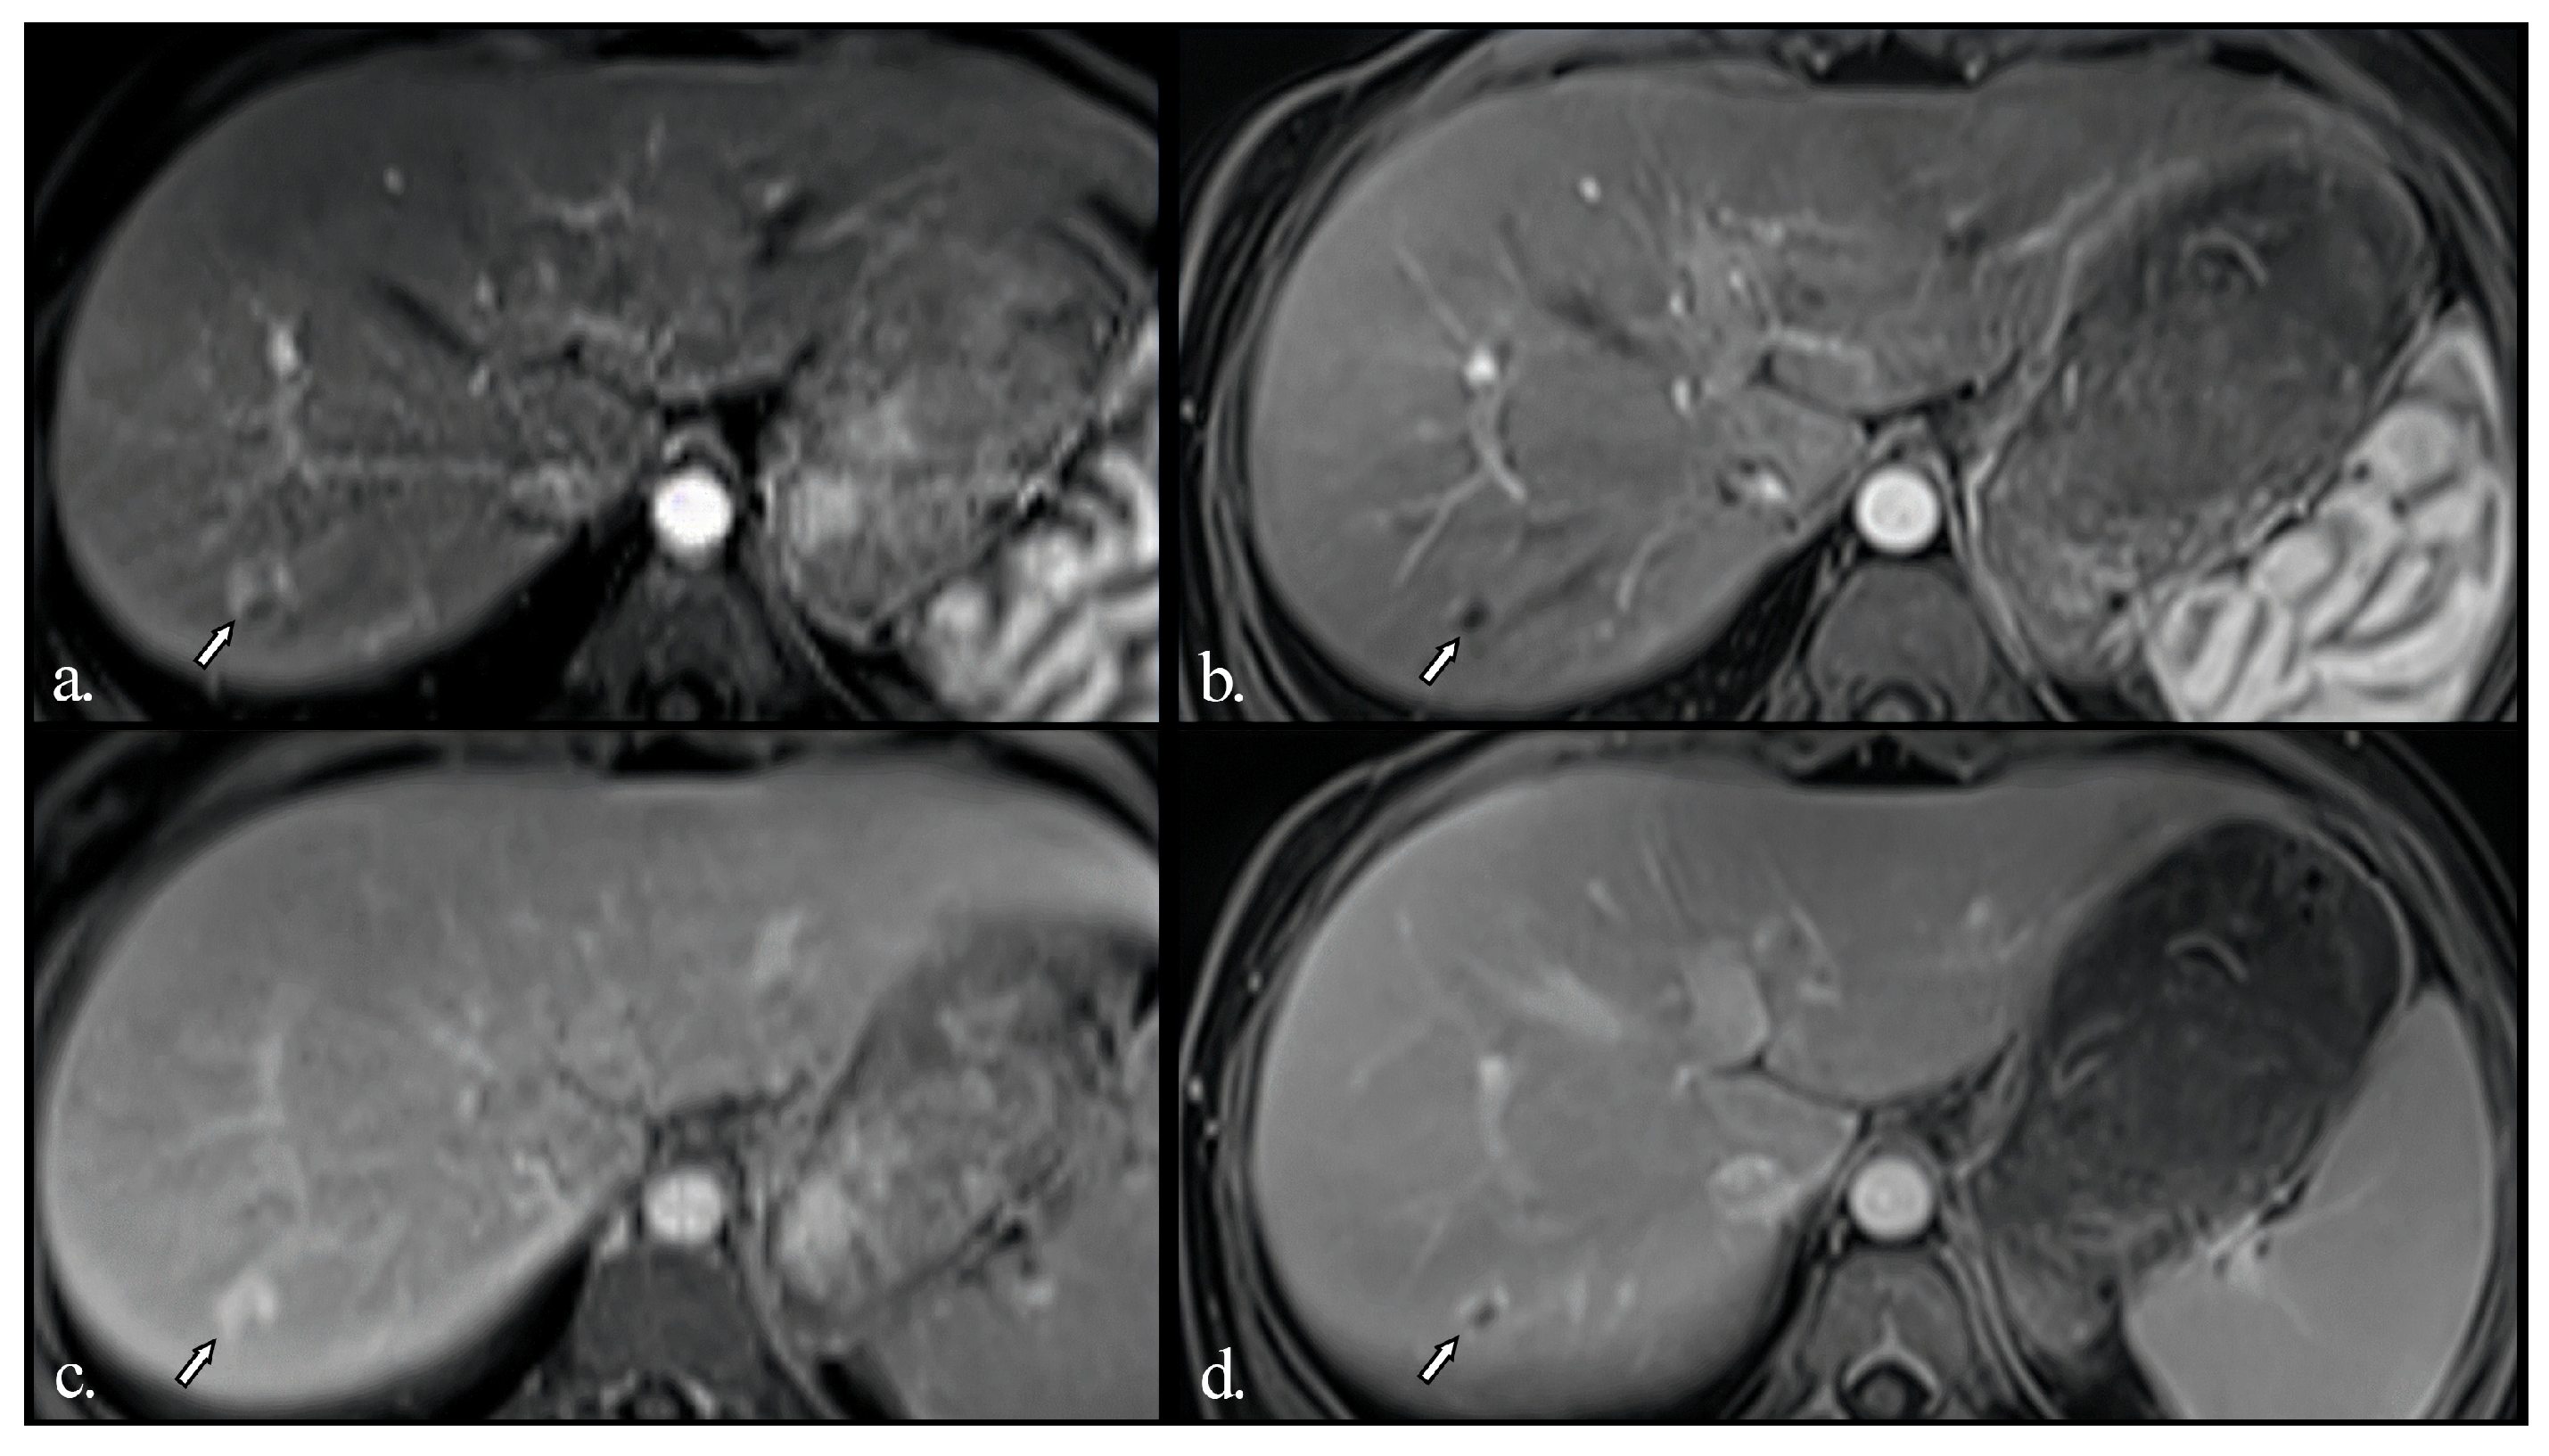

MRI showed multiple hyperenhancing focal lesions visible in the arterial phase, disseminated throughout the entire hepatic parenchyma; most were isointense on T2w and native T1w images, iso- or hyperintense in the late phase, with no washout. The lesions were relatively similar in size (10–25 mm) and imaging features (Figure 2).

An MRI was also performed in our patient to provide a more detailed characterisation of the hepatic nodules. Multiple hyperenhancing focal lesions were identified during the arterial phase; most appeared isointense on T2-weighted and native T1-weighted images and iso- to hyperintense in the late phase, without evidence of washout. The nodules were relatively uniform in size and imaging appearance. Typical native and post-contrast features consistent with FNH were present in most lesions, except for two nodules that were T1 hypointense and T2 hyperintense. This finding suggests some heterogeneity among large regenerative nodules that do not always conform to classical imaging patterns. Given that these nodules also regressed during follow-up under therapy, they are unlikely to represent a different pathology. The native T1 hypointensity and T2 hyperintensity most likely reflect increased water content within the lesions, without a specific underlying cause.

Figure 2. Initial MRI examination of the liver. (a) Native T2-weighted; (b) Native fat-saturated T1-weighted; Gd-enhanced fat-saturated T1-weighted in the arterial (c) and late (d) phases. Multiple hyperenhancing focal lesions are visible in the arterial phase (arrows, asterisks), most are isointense on T2w and native T1w images, iso- or hyperintense in the late phase, with no washout. The lesions are relatively similar in size (10 to 25 mm) and imaging features. Two of the lesions (asterisks) are slightly hyperintense on T2w and hypointense on native T1w, while still enhancing after Gd injection.

Conversely, larger or macro regenerative nodules (LRN) or FNH-like lesions show arterial hyperenhancement but no late-phase washout. They are typically similar in native and post-contrast features to FNH nodules, which are mostly found in adult women. Still, they are usually multiple, relatively homogeneous in size, and seem to have arterial flow overexpression as the leading cause. Usual MRI features of these nodules include: iso- to hypointensity on T2-weighted (T2w) images, iso- to hyperintensity natively on T1w images, no diffusion restriction, homogenous or “spoke-wheel” enhancement in the Gd-enhanced arterial phase, and no wash-out in the venous and late phase. A central scar with arterial hypoenhancement and late-phase enhancement can also be common [11,23]. The use of hepato-biliary contrast (i.e., Gadoxetic acid) will show either isoenhancement or hyperenhancement in the hepato-biliary phase, which can help distinguish from hepatocellular carcinoma or liver adenoma (where some wash-out is to be expected in the hepato-biliary phase) [11,13,24,25].